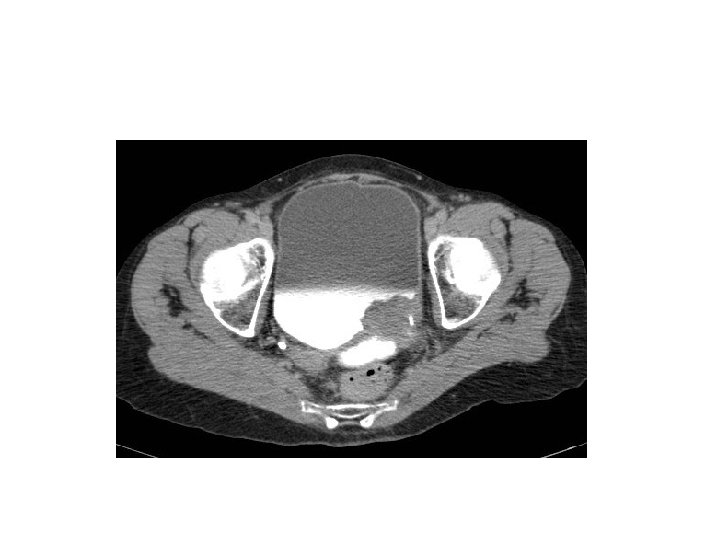

Hematuria work up 1 - flexible cystoscopy 2 - upper tract imaging ( CT urogram) 3 - others like urine cytology

ultrasound